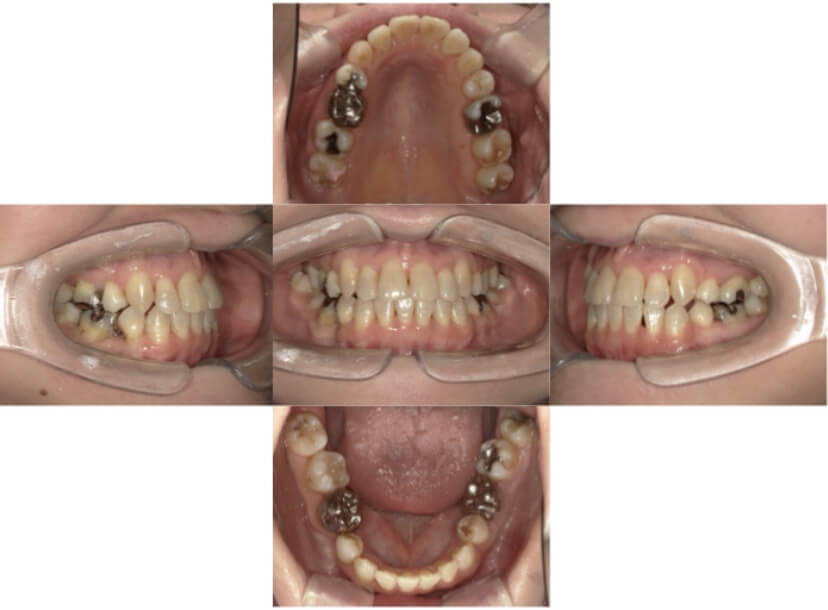

症例1

上顎前突、叢生

抜歯

ブラケット矯正

上下顎叢生、上顎前突(出っ歯、上下の前歯のガタガタ)のケースです。

装置はラビアル(上下表側)で、上顎の小臼歯を2本抜歯を行っています。抜歯したスペースを使って、上の前歯の後方移動と叢生(ガタガタ)と出っ歯の改善を行っています。下は歯と歯の間にIPR(隣接面削合)を行い、スペースを確保し、叢生の改善を行っています。

主訴 前歯のガタガタと出っ歯が気になる。

年齢・性別 47歳 女性

お住まいの地域 神奈川県川崎市

治療方針 抜歯スペースおよびIPRを利用して上前歯の叢生(ガタガタ)の改善

抜歯部位 上顎左右第一小臼歯

使用装置 ラビアル(上下表側)、顎間ゴム

治療期間 2年0か月

治療回数 15回

リテーナー クリアリテーナー

BEFORE

AFTER